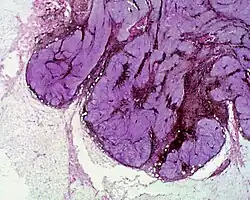

• A cellular blue nevus is a cutaneous condition characterized by large, firm, blue or blue-black nodules.[7]:701

Histopathology